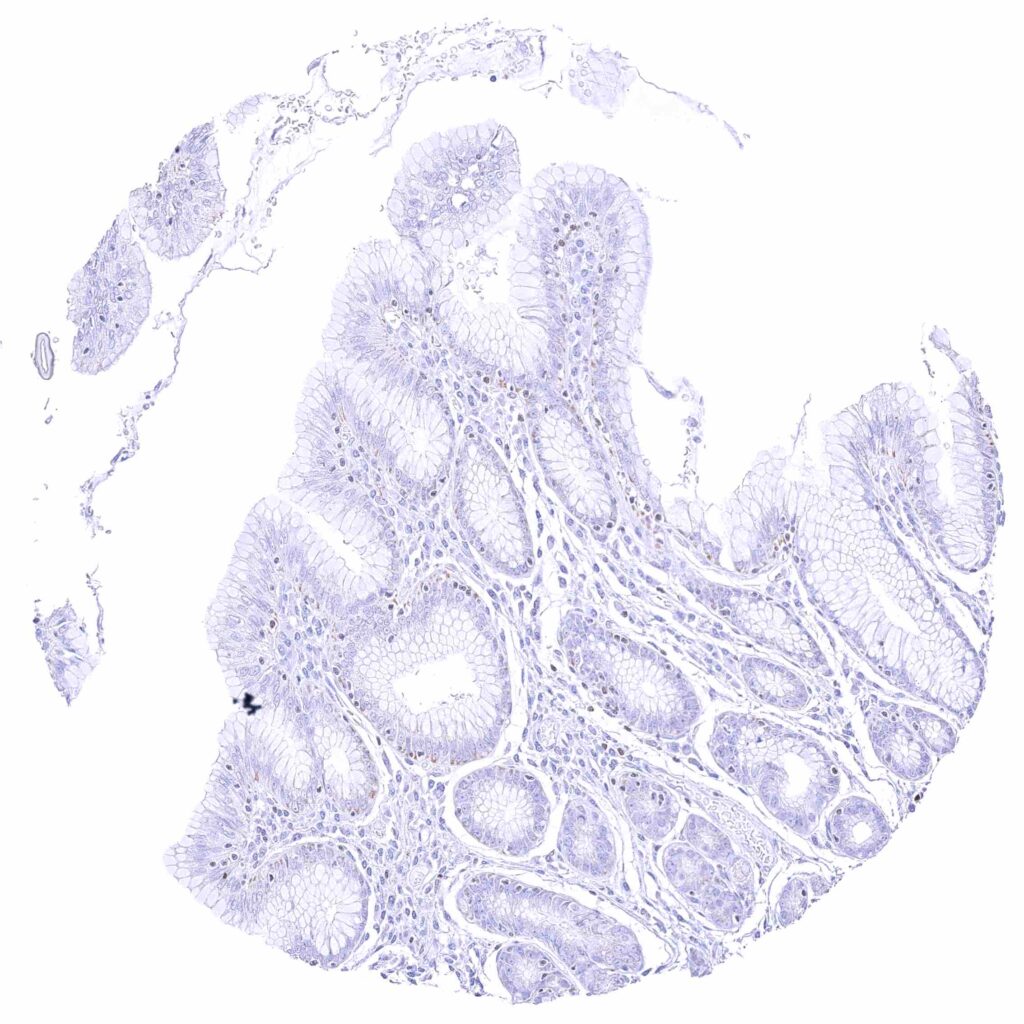

Colon descendens, mucosa – Nuclear GATA3 positivity of few lymphocytes. Faint cytoplasmic GATA3 positivity of some epithelial cells.

Rectum, mucosa – Nuclear GATA3 positivity of some lymphocytes. Granular cytoplasmic GATA3 staining of epithelial cells.